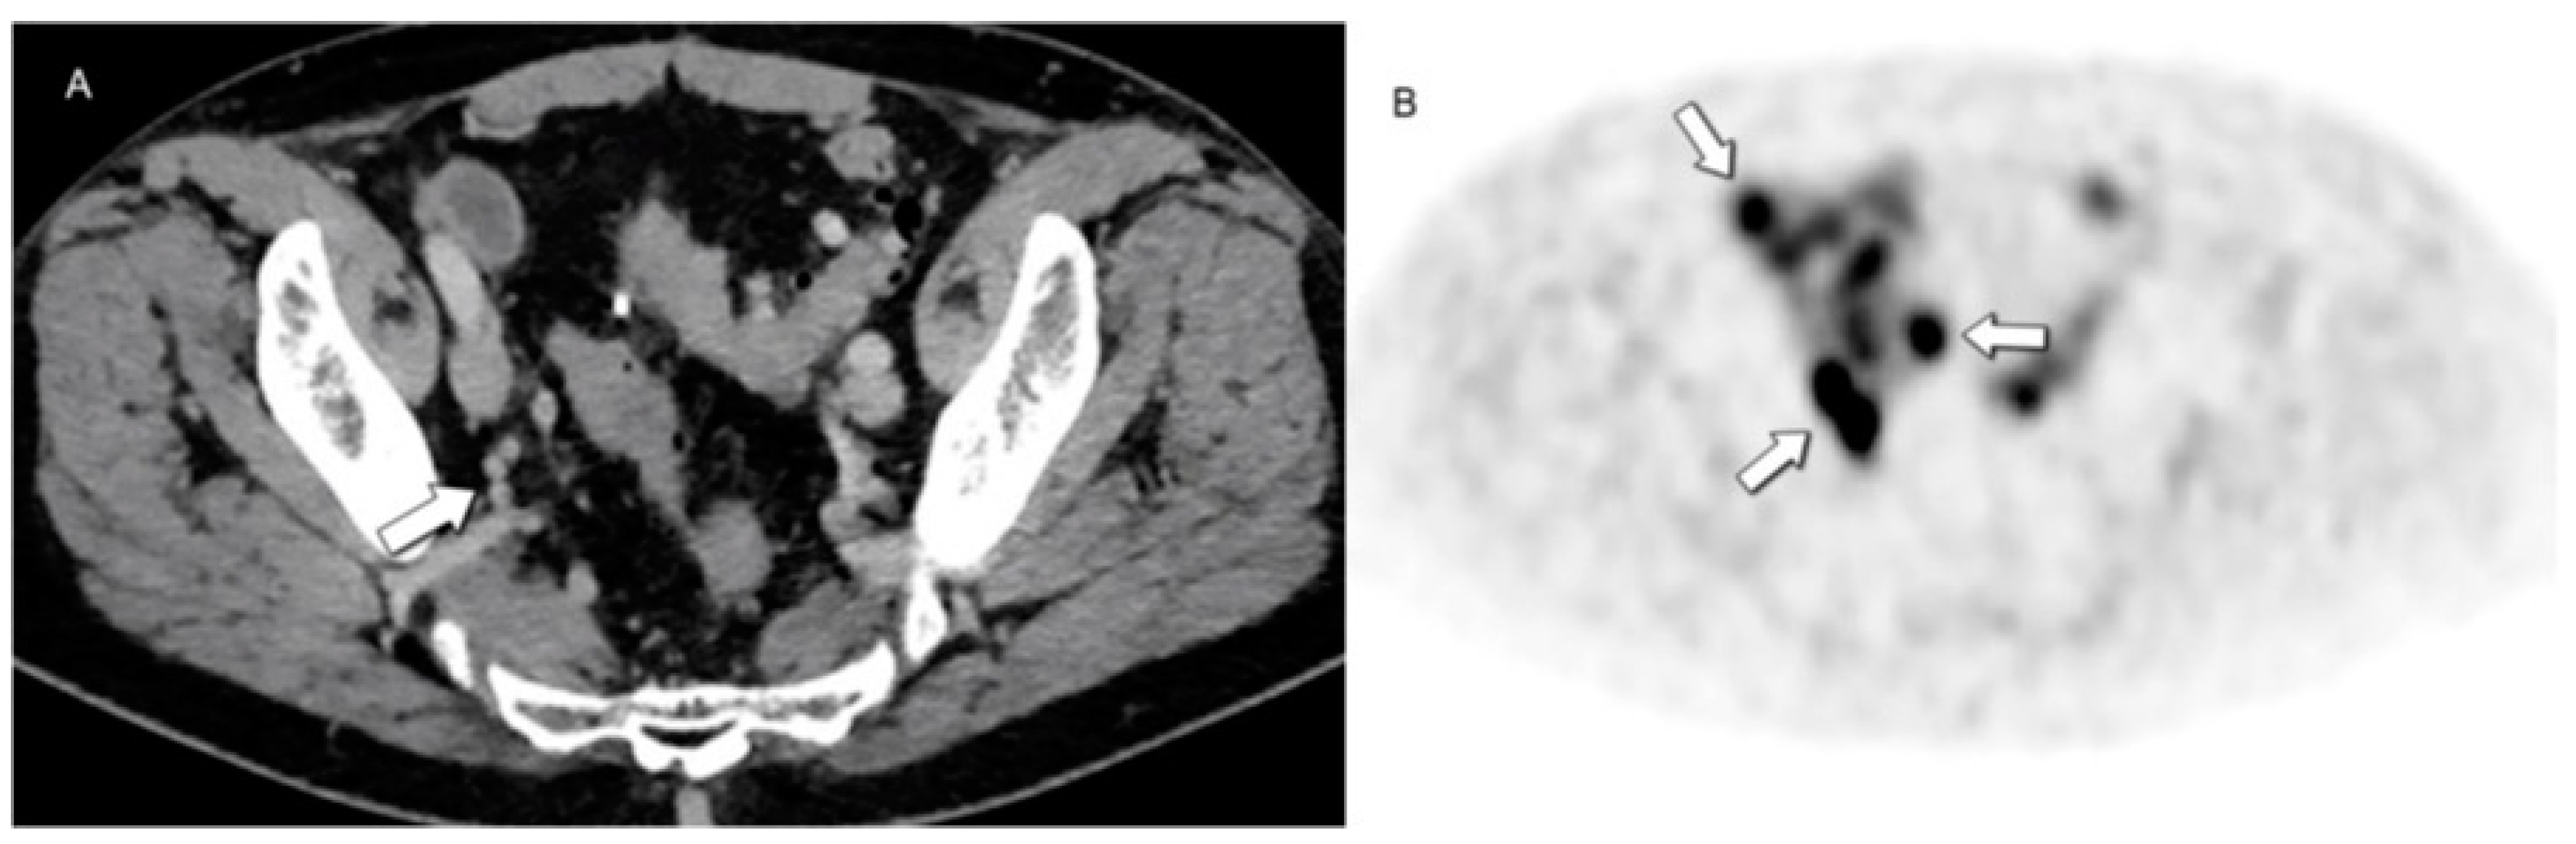

- Karfis, I.; Marin, G.; Levillain, H.; Drisis, S.; Muteganya, R.; Critchi, G.; Taraji-Schiltz, L.; Guix, C.A.; Shaza, L.; Elbachiri, M.; et al. Prognostic Value of a Three-Scale Grading System Based on Combining Molecular Imaging with 68Ga-DOTATATE and 18F-FDG PET/CT in Patients with Metastatic Gastroenteropancreatic Neuroendocrine Neoplasias. Oncotarget 2020, 11, 589–599. [Google Scholar] [CrossRef] [PubMed]